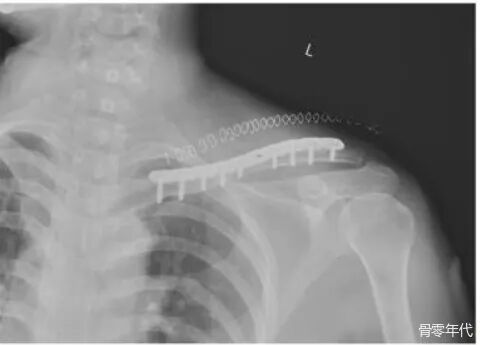

术前X线检查提示左锁骨中段骨折,移位明显。术后X线:显示内固定到位,骨折对位良好。术后4个月X线片:骨折线仍清晰可见,提示骨折愈合延迟。术后11个月X光片:骨折线仍然清晰可见,这可能表明骨折尚未完全愈合或愈合过程停滞。术后17个月X光片:未见明显骨折线,通常表示骨折已愈合。拆除内固定后:骨折端移位,这意味着发生了骨折。切开复位和骨移植内固定后的X射线。